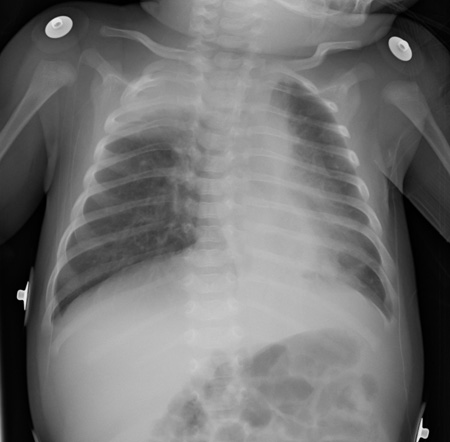

Reveals atelectasis, hyperinflation, peribronchial cuffing, and infiltrate.[Figure caption and citation for the preceding image starts]: AtelectasisFrom the personal collections of Melvin L. Wright, DO and Giovanni Piedimonte, MD; used with permission [Citation ends].

[Figure caption and citation for the preceding image starts]: Air trapping and peribronchial cuffingFrom the personal collections of Melvin L. Wright, DO and Giovanni Piedimonte, MD; used with permission [Citation ends].

Should be reserved for those patients with severe disease, and those who do not improve at the expected rate.[2][114]

The National Institute for Health and Care Excellence recommends only performing a chest x‑ray if intensive care is being proposed for a baby or child. A chest x‑ray in babies or children with bronchiolitis may mimic pneumonia and should not be used to determine the need for antibiotics.[53]

atelectasis, hyperinflation, peribronchial cuffing, infiltrate